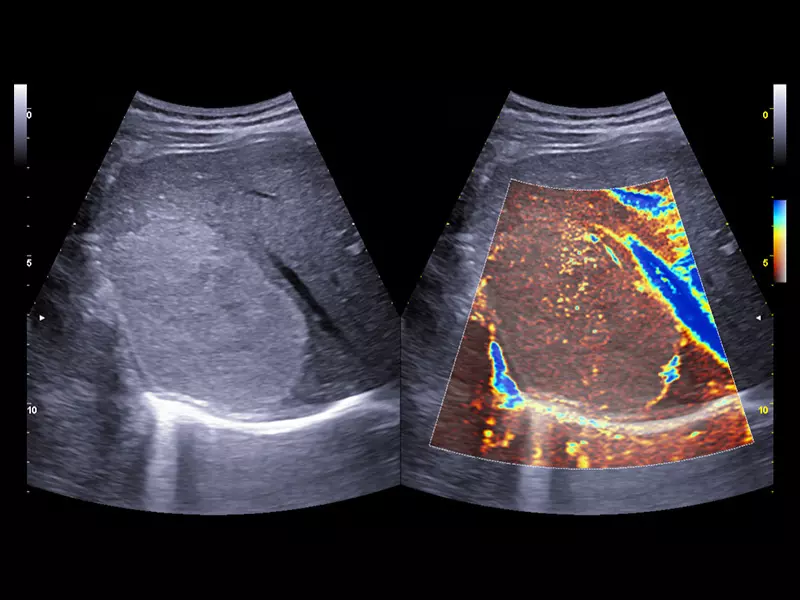

MyLab™Sigma - Kidney perfusion with high sensitivity Color Doppler mode

MyLab™Sigma - Kidney perfusion with high sensitivity Color Doppler mode